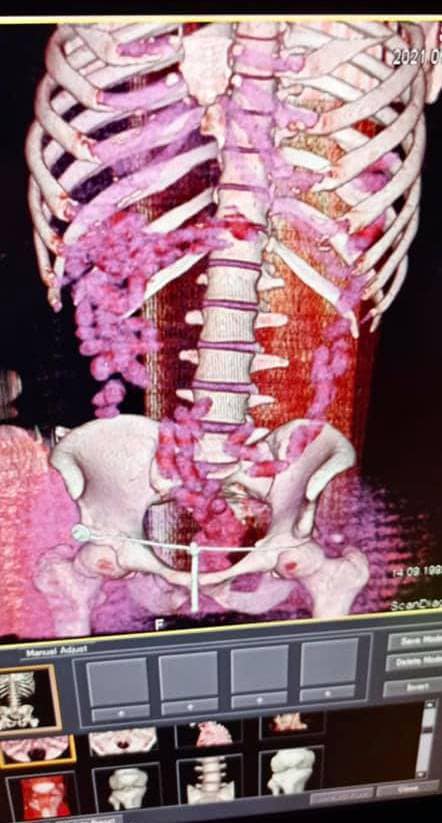

"В июле 2021 года в Борисполе был задержан бразилец, который в желудке ввез в Украину почти 1 кг кокаина. Мужчина проглотил 90 капсул, которые извлекали из кишечника медикаментозным путем после компьютерной томографии", - говорится в сообщении.

Напомним, 29-летний курьер с начиненными кокаином капсулами в желудке прибыл в аэропорт "Борисполь". Имея предварительную оперативную информацию, таможенники применили в отношении иностранца личный досмотр с привлечением медицинского работника. Процедура проходила в медицинском учреждении с применением компьютерной томографии брюшной полости мужчины.

Изъятие 90 капсул овальной формы, которые находились в его кишечнике, происходило медикаментозным путем и длилось почти три часа.